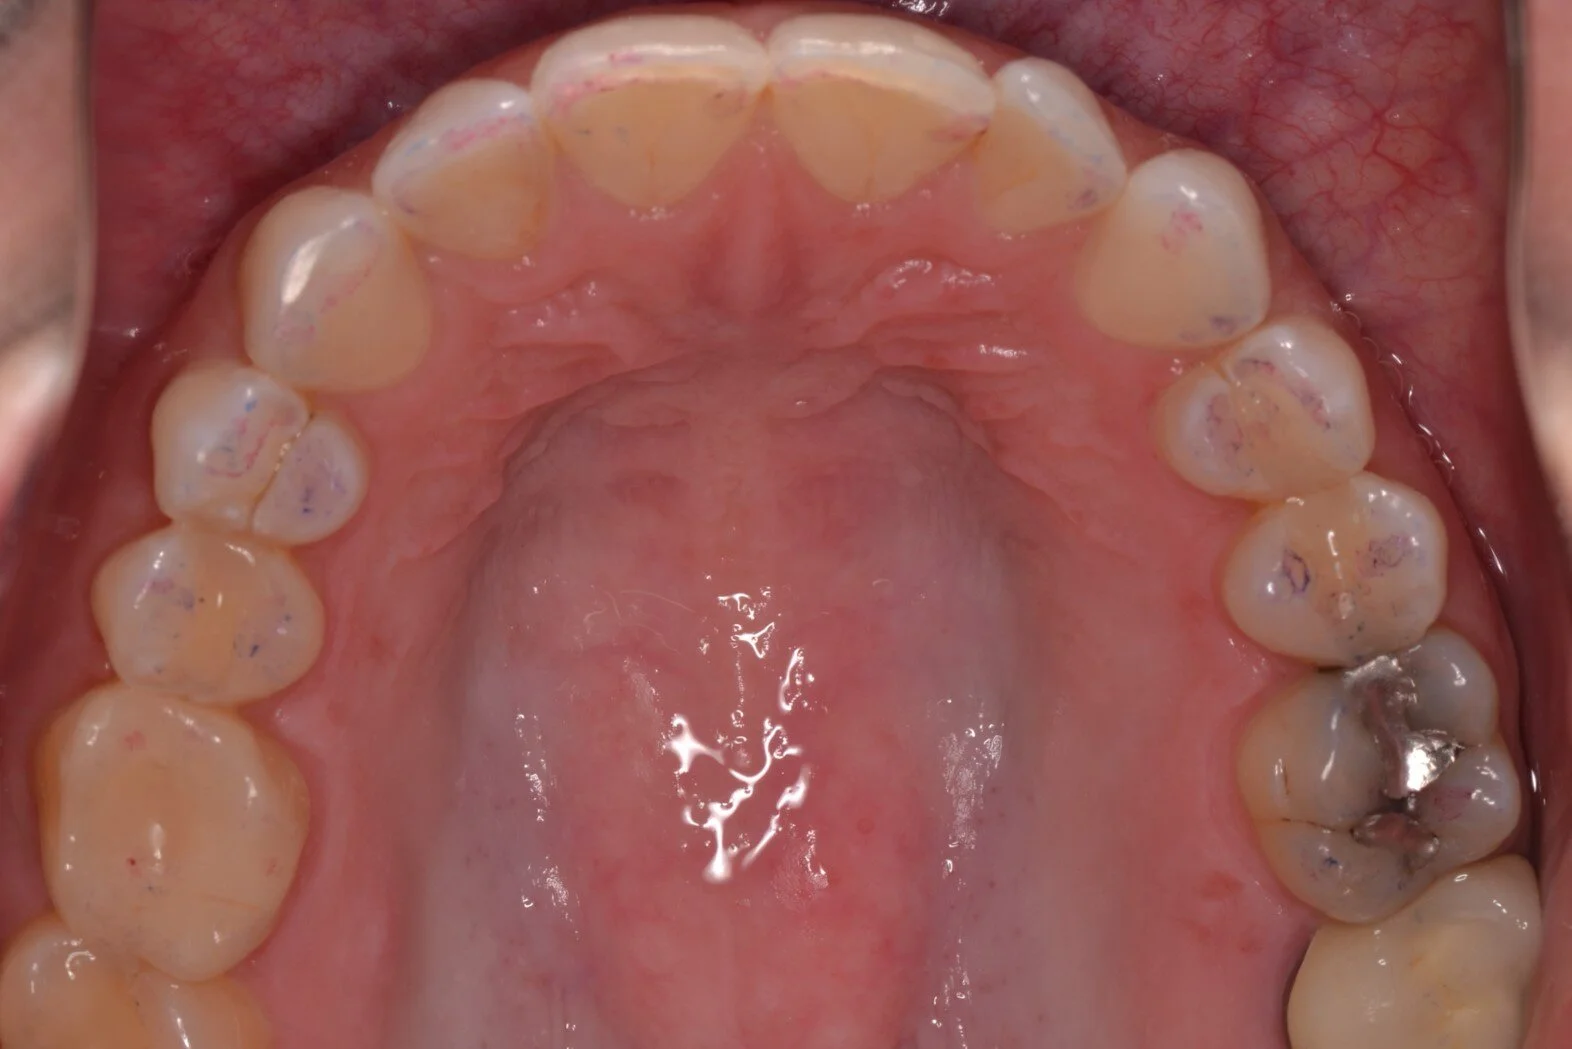

Figure 5g; Adjacent grouping of all ceramics placed in situ.

After the ceramics have been evaluated and verified for fit and composition on a stone model, individual ceramics are placed intra-orally to confirm marginal fit using visual evaluation and tactile inspection with a dental explorer (figure 5a, 5b). After the marginal adaptation and fit of each restoration is confirmed to be satisfactory, all restorations are placed onto the respective preparations with a water soluble glycerin based try-in paste (Variolink Esthetic, Ivoclar Vivadent) to evaluate interproximal contacts and the esthetic presentation of the adjacent grouping in situ (figure 5c, 5d, 5e, 5f, 5g). The advantage to the try-in pastes is two-fold. First, the paste will retain the restorations well enough for the patient to evaluate the shade and shape of the teeth, and the composition of the new smile. The patient should examine the ceramics in different light sources to ensure the effects of metamerism will not dramatically or adversely influence the shade presentation of the restorations. Second, the try-in paste will offer a replica of the final cement shade and any influence it may impart of the optics of the final restorations, namely the quality of color relating to value. In this case, the operator has three choices of try-in cements: “neutral,” which is desirable as it will impart no change on the presentation of the ceramics; “warm,” to lower the value if the restorations appear to bright; and “light,” to increase the value of the restorations if they appear to dull. The final resin cement should match the try-in paste that was confirmed during the trial arrangement. The try-in pastes are water soluble, and will rinse away will no effect on the final bond strength.